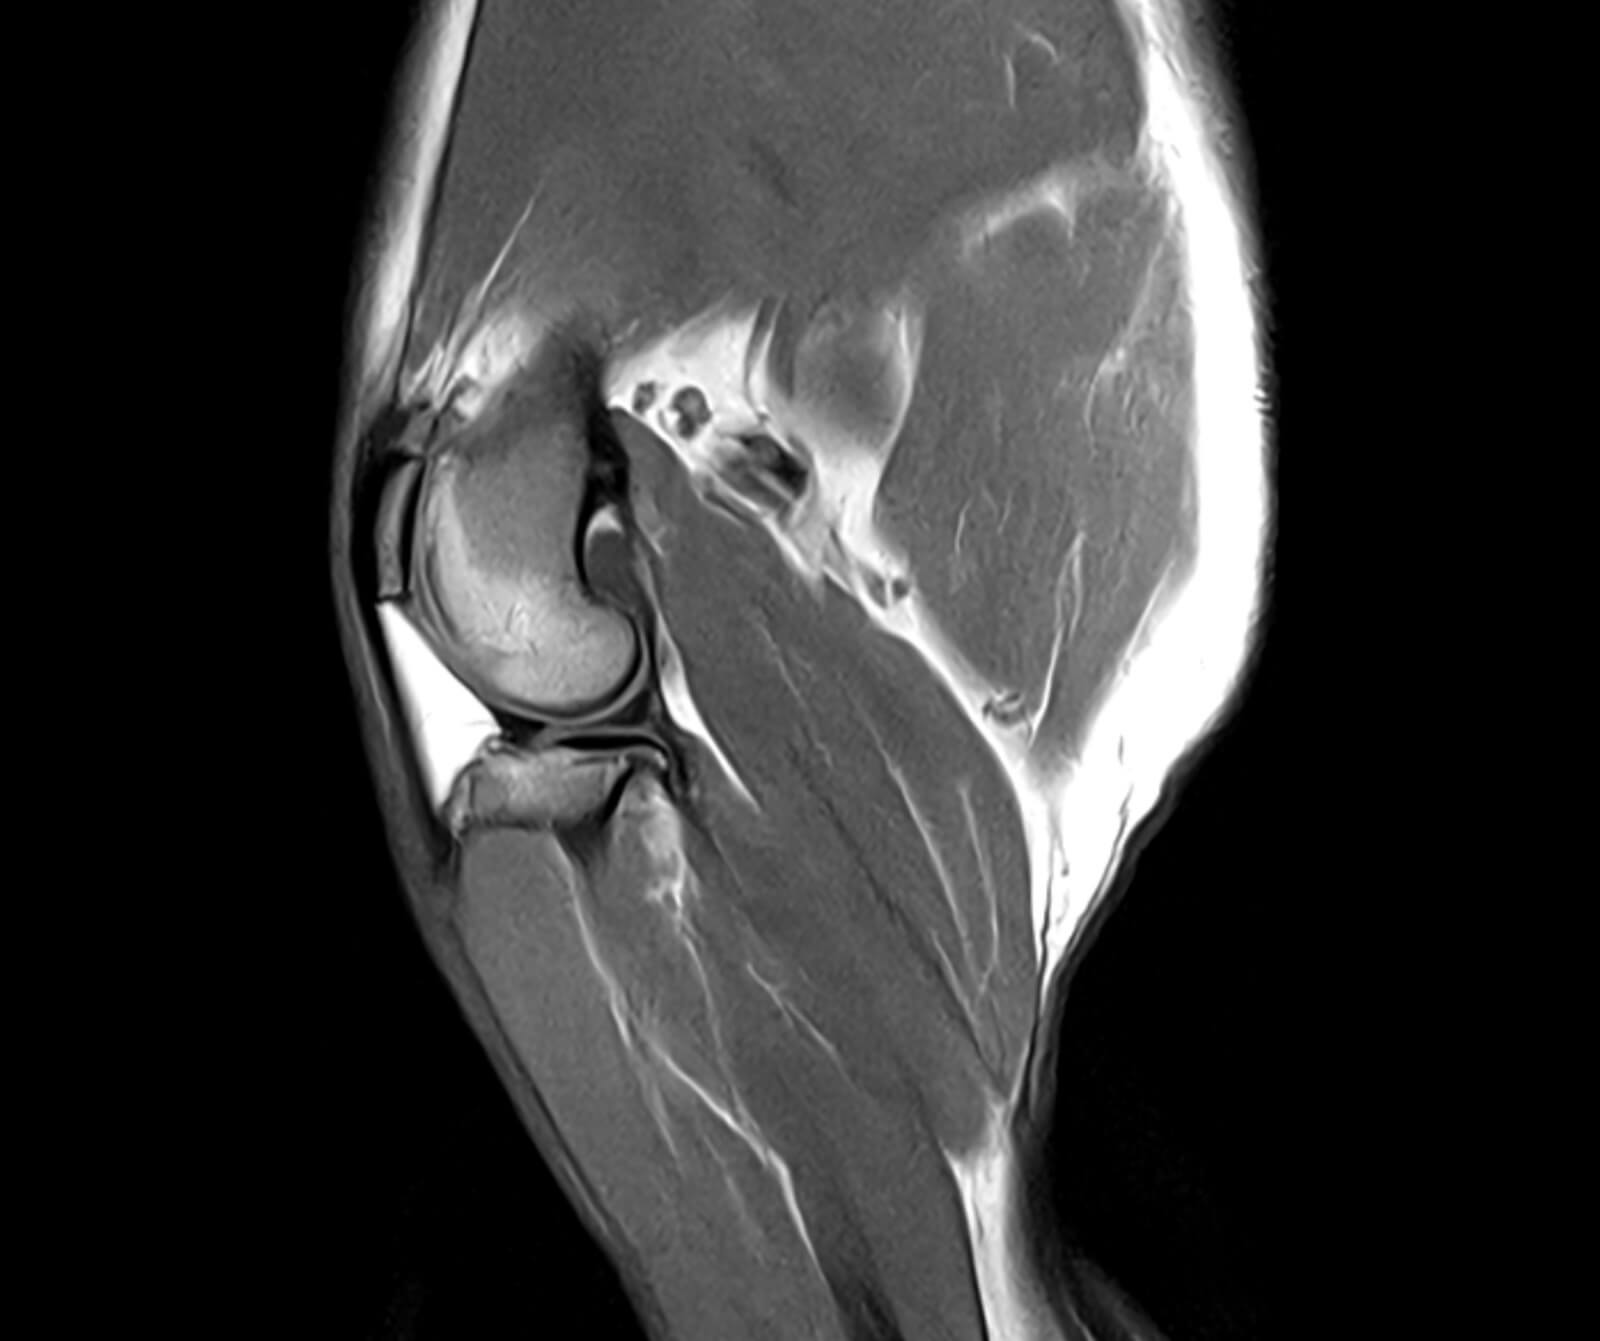

• Eklem, bağ ve tendon yaralanmaları

• Kas, bağ, tendon ve eklemler gibi yumuşak dokular